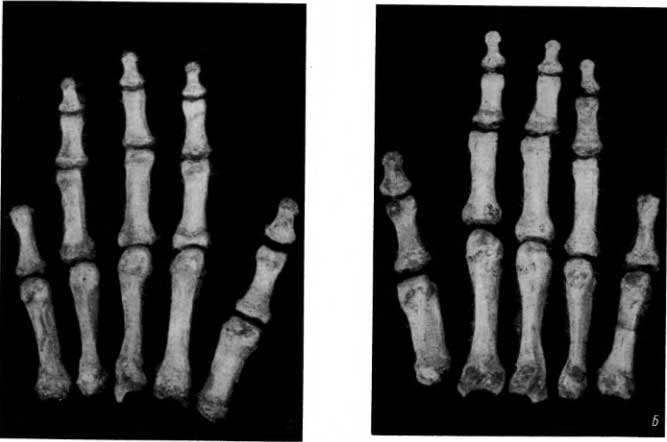

Рис. 112. A — короткие трубчатые кости правой кисти женщины эпохи мезолита (ладонная сторона), усеченный мизинец; Б — состояние тех же костей на левой руке.

Это усечение могло быть произведено за год или скорее за несколько лет до смерти этой молодой женщины. Во всяком случае обрубками V пальцев эта женщина в какой-то мере пользовалась, когда работали ее руки. Проявления бездеятельности (в частности, в виде разрежения структуры кости — остеопороза), которые должны были наблюдаться в течение первого года после усечения, исчезли. Мы видим структуру несколько менее нагружаемой, но работающей кости (рис. 113).

Рис. 113. Трубчатые кости 4-го и 5-го пальцев в рентгеновском изображении (справа — кости правой кисти, слева — кости левой кисти).